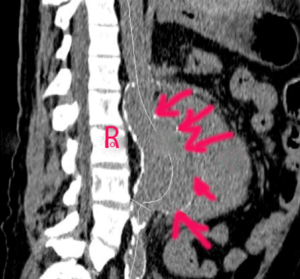

L’image caractéristique est le flap intimal, témoin du décollement de l’intima.

On observe une bande échogène dans la lumière supposée de l’aorte abdominale. L’examen s’attachera à retrouver l’origine de la dissection (voir aorte thoracique).

Les mesures effectuées sur un anévrisme doivent inclure le diamètre total incluant le thrombus (flèche bleue) et la lumière. Les images suivantes montrent un anévrisme majeur de 8cm partiellement thrombosé. Il est possible d’utiliser le doppler couleur dans ces circonstances, ce qui permettra d’objectiver l’absence de flux au niveau de la thrombose. L’examen sera complété par une coupe sagittale afin de préciser l’étendue de l’anévrisme (seconde image).